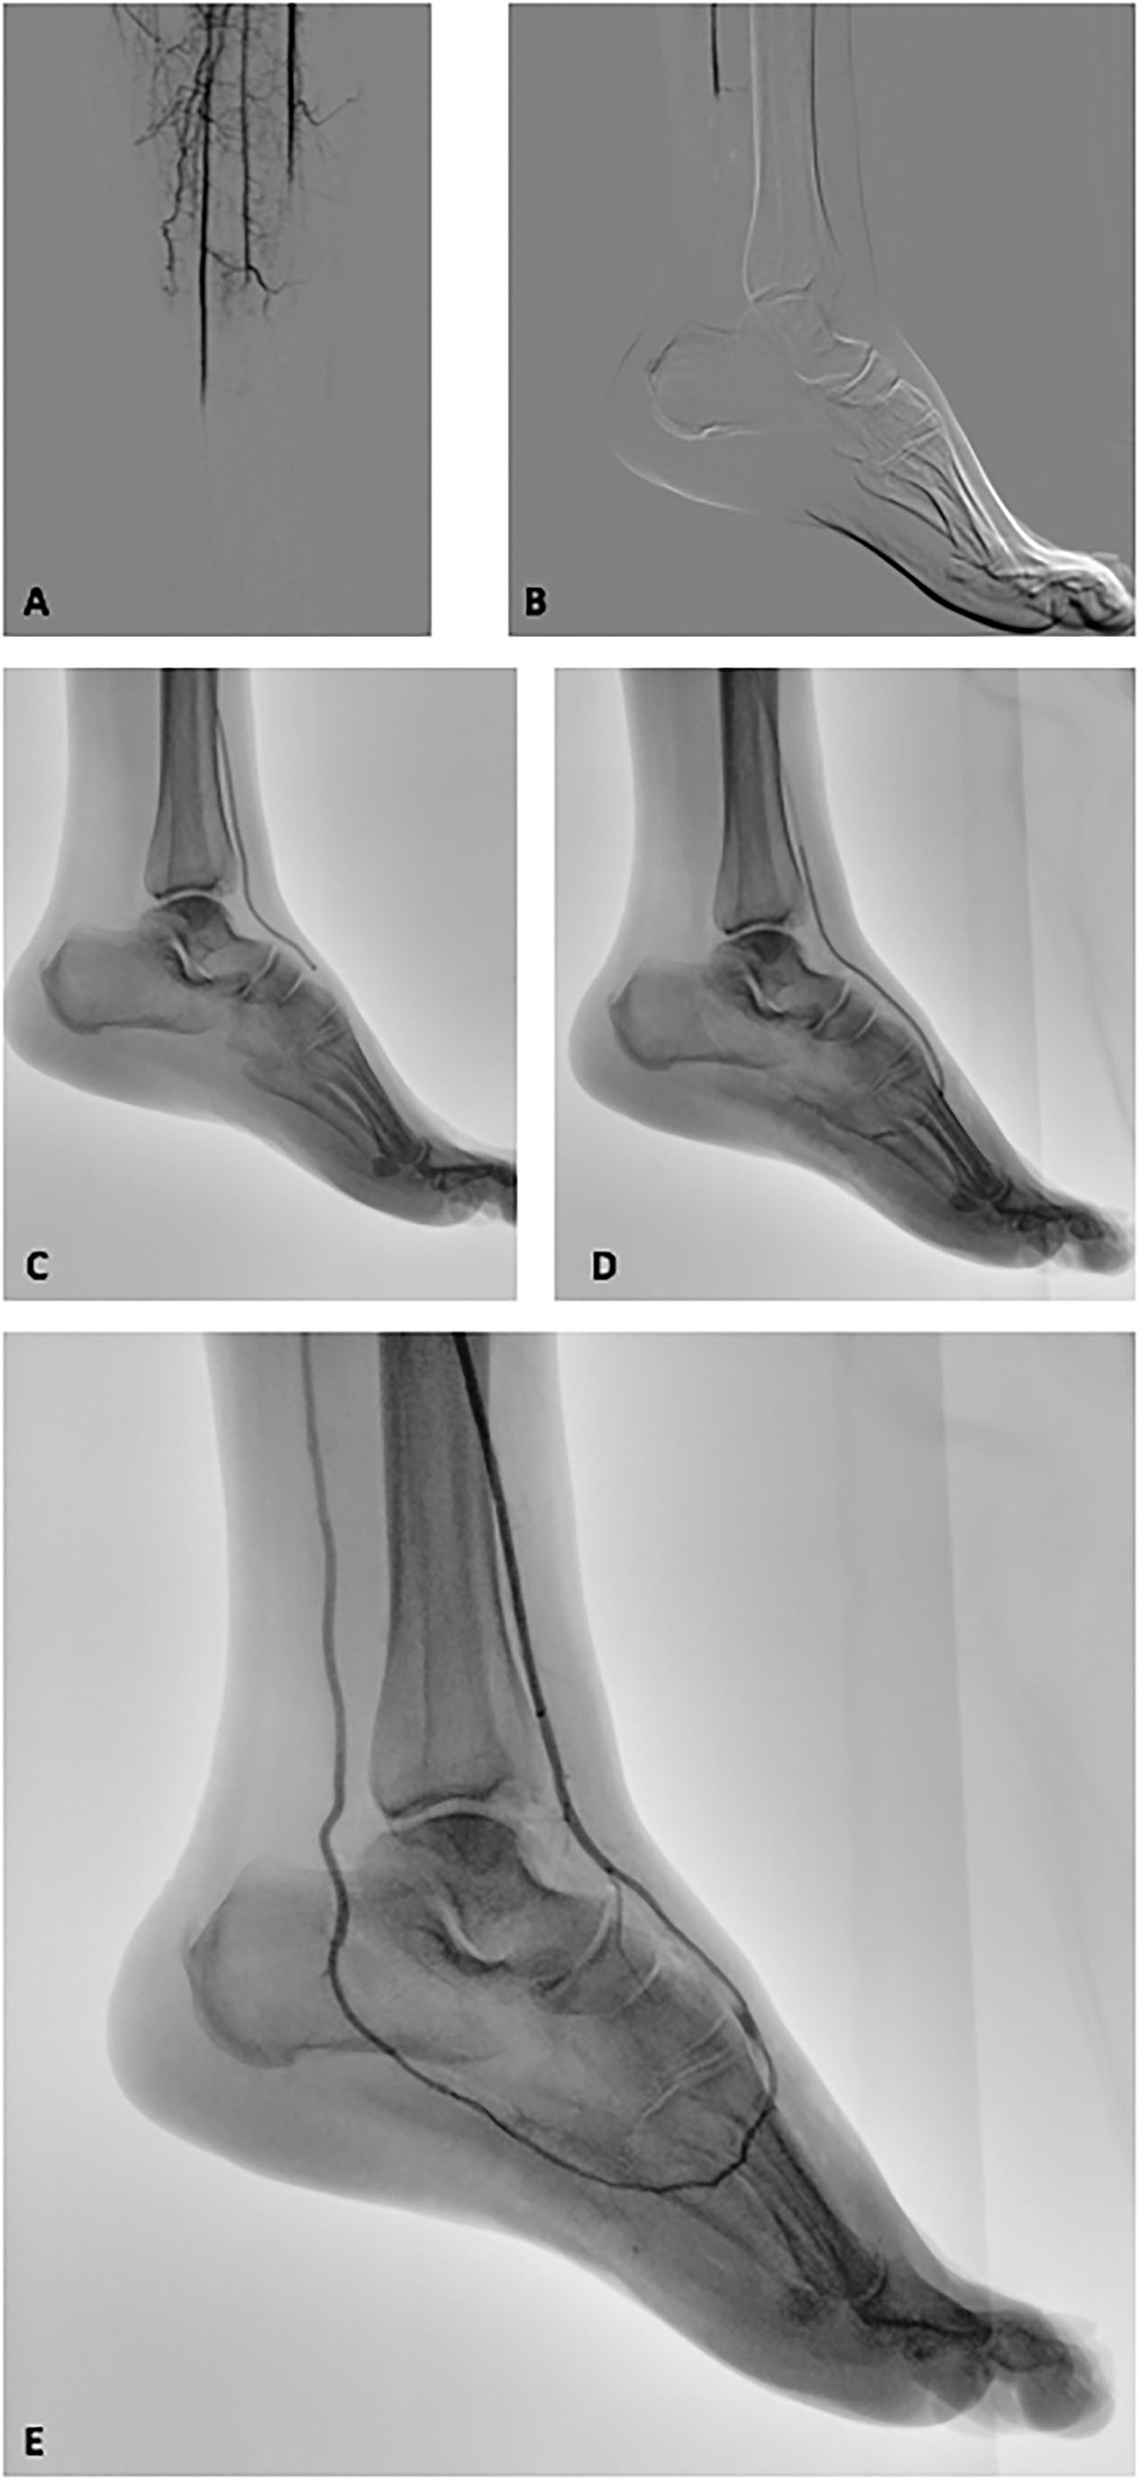

Endovascular catheter thromboaspiration maneuvers with Indigo CAT 6 + SEP 6 (Penumbra Inc, Alameda, CA, USA) system were performed with removal of organized thrombotic material. The recanalization procedure achieved a good result, reaching the more distal part of the foot arterial tree using the plantar loop technique (3) (Figure 1). Although that maneuver was successful to reestablish the flow at level of plantar arch, no flow was appreciated into digital arteries. In order to achieve the complete resolution of the ischemia, the surgical team decided to start a 24-h local catheter-directed thrombolysis (CDT) with recombinant Tissue-Plasminogen-Activator. A 24- and 48-h angiography revealed the same situation of severe delay of the contrast medium washout at below-the-ankle vessels with near-complete absence of digital arteries and microvessel perfusion of the foot (Figure 1).

Figure 1

Intraoperative fluoroscopic images of the revascularization procedure of the ischemic lower limb. (A,B) Intraprocedural angiography revealed a below-the-knee complete occlusion on all the tibial vessels and a complete absence of distal foot perfusion. (C) Penumbra Indigo thromboaspiration catheter CAT 6 advanced in the anterior tibial artery and dorsalis pedis. (D) Thromboaspiration catheter CAT 6 advanced into the plantar arch. (E) Post-thromboaspiration angiography revealed the complete recanalization of the anterior tibial artery, dorsal, and plantar arch and posterior tibial artery. A near-complete absence of interdigital arteries and distal vasculature opacization is also highlighted.